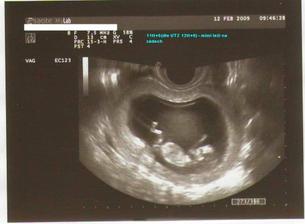

12.2.09 - poradna + těhotenská průkazka + odběry

12.2.09 - mám průkazku, mimi OK, vše v normě, dle PM 11tt+6, dle UTZ 12tt+0, měří 5,5 cm (bez nožiček) - mrskalo sebou, plavalo, přetáčelo se, nádherný pohled 🙂, TK 120/70 , náběry krve